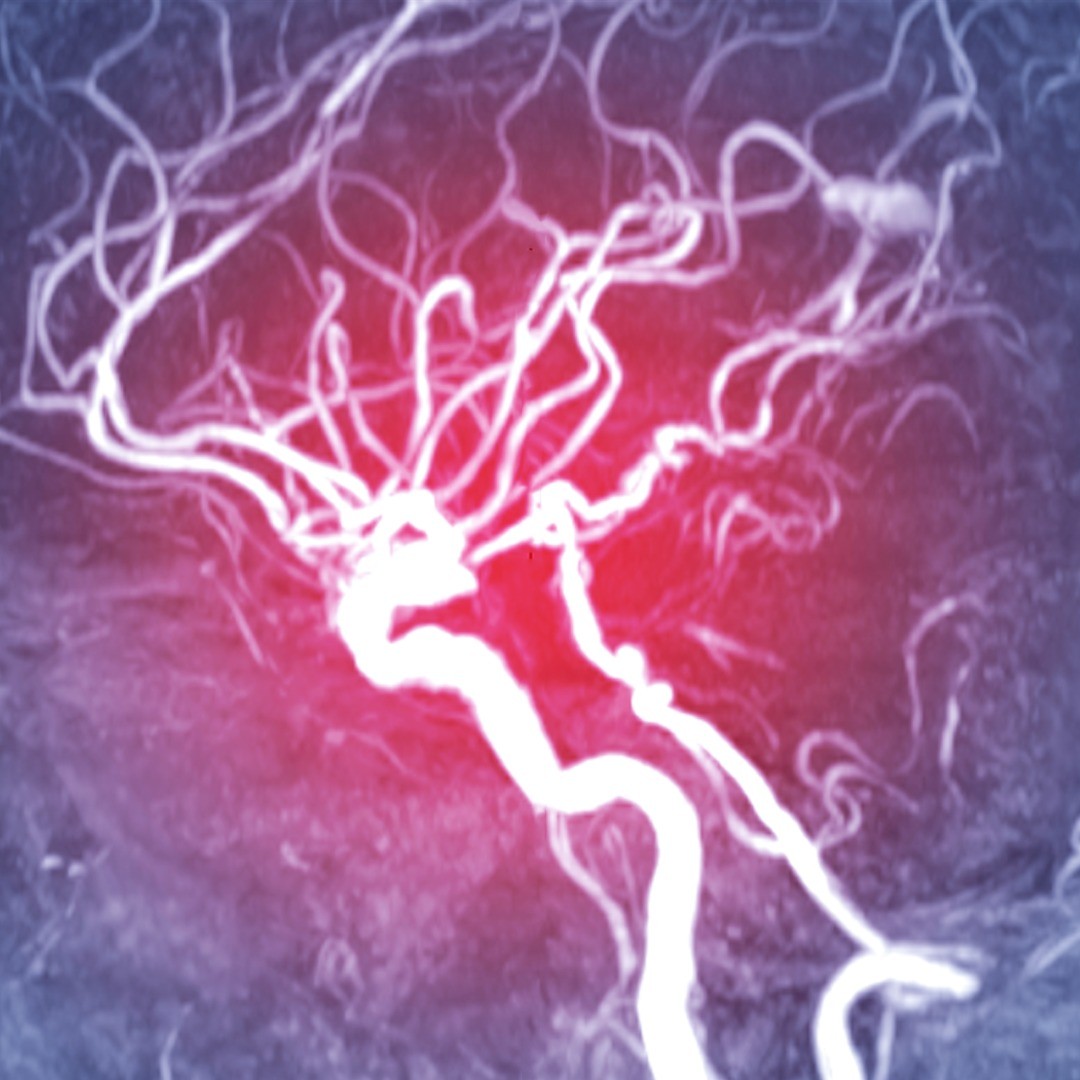

Brain aneurysm clipping is performed to treat an aneurysm, a bulge in the wall of an artery, inside the skull. This weak space in the blood vessel wall can become so engorged with blood that it ruptures or leaks. A subarachnoid hemorrhage occurs when there is bleeding (hemorrhage) underneath(sub) the arachnoid mater, one of the protective coverings of the brain. Immediate emergency care is needed in the case of a subarachnoid hemorrhage.

The purpose of microsurgical aneurysm clipping is to halt blood flow to an intracranial aneurysm and preventing it from bursting and causing a subarachnoid hemorrhage. In this procedure, a small, metal surgical clip is applied to the base of an aneurysm to prevent blood leakage. The procedure can also be used after an event, or rupture of an aneurysm.